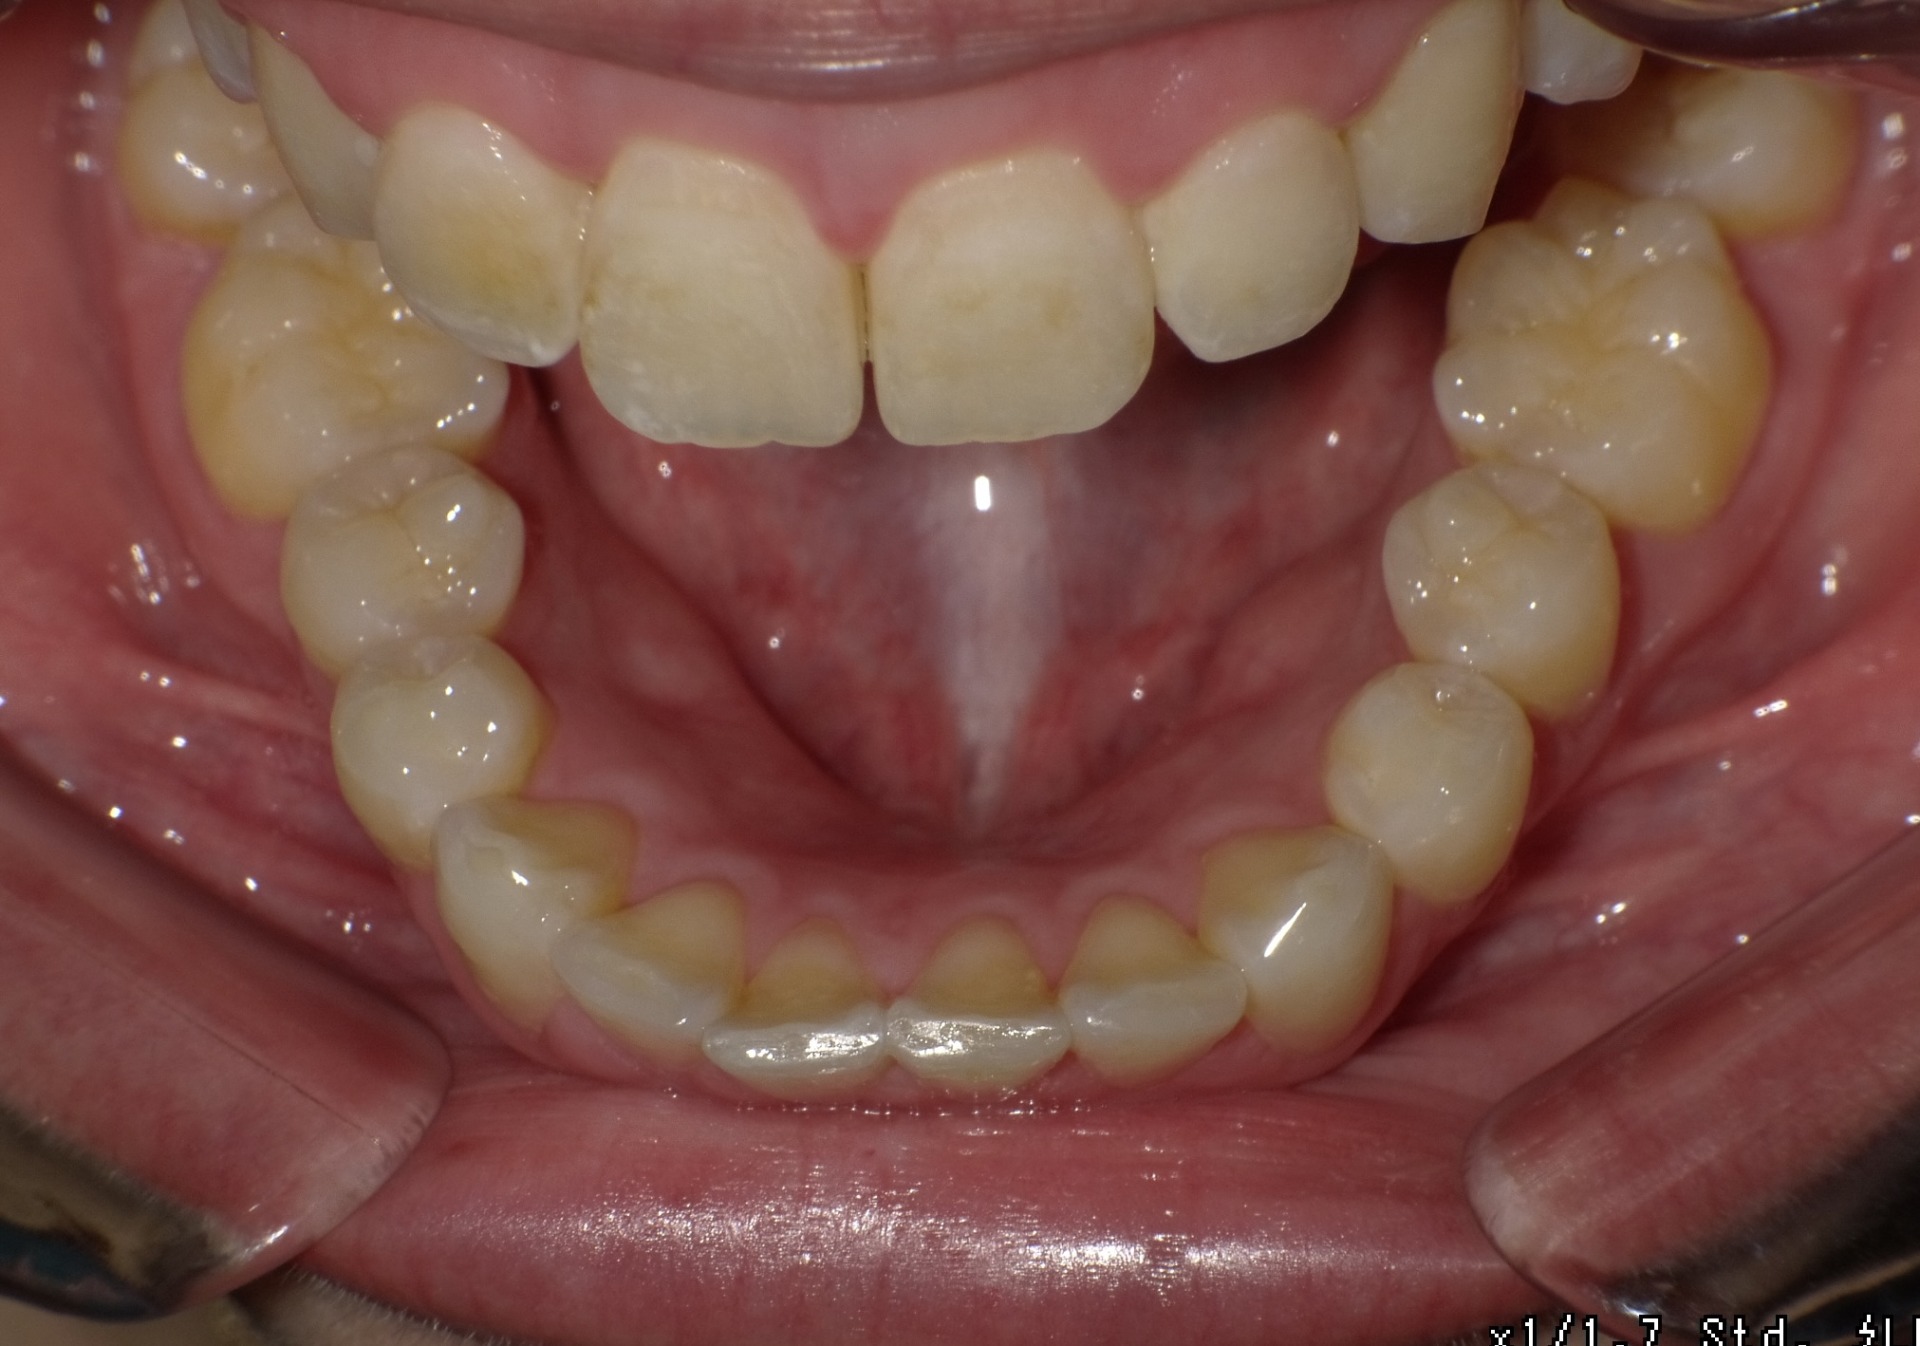

After